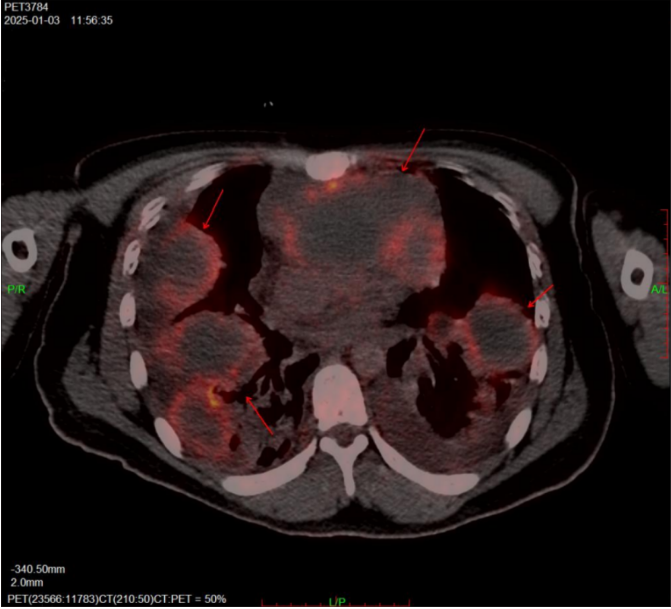

该男性患者,22岁,来自衡阳,因发现前纵膈肿物伴双肺多发病变转入中南大学湘雅三医院进一步诊疗。入院后,患者在CT引导下接受了右上肺肿块穿刺活检术,但病理结果未见恶性肿瘤证据。随后,患者病情迅速恶化,表现为呼吸困难、心率及呼吸急促,血氧饱和度吸氧状态下仍低于94%,伴有间断发热、气促、咳痰及无法平卧,初步考虑前纵膈肿物压迫纵膈大血管并合并肺部感染。为尽快明确病因并制定治疗方案,需尽早完善PET-CT检查。然而,由于患者病情危重且无法平卧,检查实施难度极大。

在病房医护人员的陪护下,患者次日上午以半坐卧位状态、持续吸氧并动态监测生命体征的情况下前往核医学科。面对这一高风险挑战,核医学科主任赵敏迅速启动应急方案。在科室医护技团队的通力协作下,患者顺利完成了PET-CT检查。最终,检查结果提示前纵膈恶性生殖细胞瘤伴双肺多发转移的可能性大,为下一步治疗决策提供了至关重要的依据。

PET-CT作为一种融合功能代谢显像(PET)与解剖结构显像(CT)优势的先进医学影像技术,可提供全身断层图像,精准定位病灶。自技术应用以来,PET-CT在肿瘤的早期发现、诊断精确性提升方面成效显著,同时为穿刺活检定位、疗效评估及预后预测提供了强有力支持。随着技术的不断进步与临床推广,PET-CT将在肿瘤诊治领域发挥更为重要的作用,为更多患者带来生命的希望。